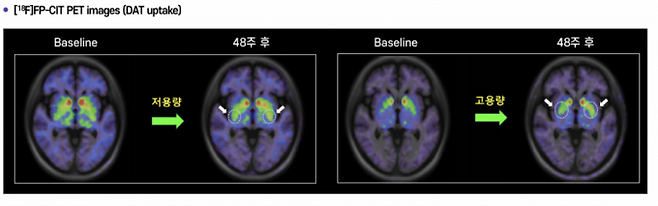

조 소장은 “중증허혈 치료제는 통증 개선에서 획기적인 결과를 얻고 있고 파킨슨병 세포치료제는 질환의 진행 자체를 되돌리는 수준의 결과를 보여주고 있다”고 강조했다. 이어 "특히 파킨슨병 치료제의 경우 줄기세포로부터 유도한 도파민 신경전구세포를 뇌에 직접 이식해 도파민 분비 기능을 회복시키는 방식인데, 이식된 세포가 체내에서 살아남아 실제로 도파민을 분비하고 환자의 운동 증상이 호전되는 것을 직접 확인했다”고 말했다.

조 소장은 “TED 플랫폼으로 제조한 신경전구세포는 블루락의 세포치료제에 비해 분화 효율과 정밀도가 훨씬 높다”며 “임상 결과에서도 도파민 분비와 운동 기능 개선 등에서 뚜렷한 치료 효과가 확인됐다”고 밝혔다.

“역시 파킨슨병 치료제다. 현재까지 나온 결과는 질환의 진행을 ‘지연’하는 수준이 아니라 실제로 ‘역행’시키는 효과가 있다. 기존 치료제로는 전례가 없는 결과다.”